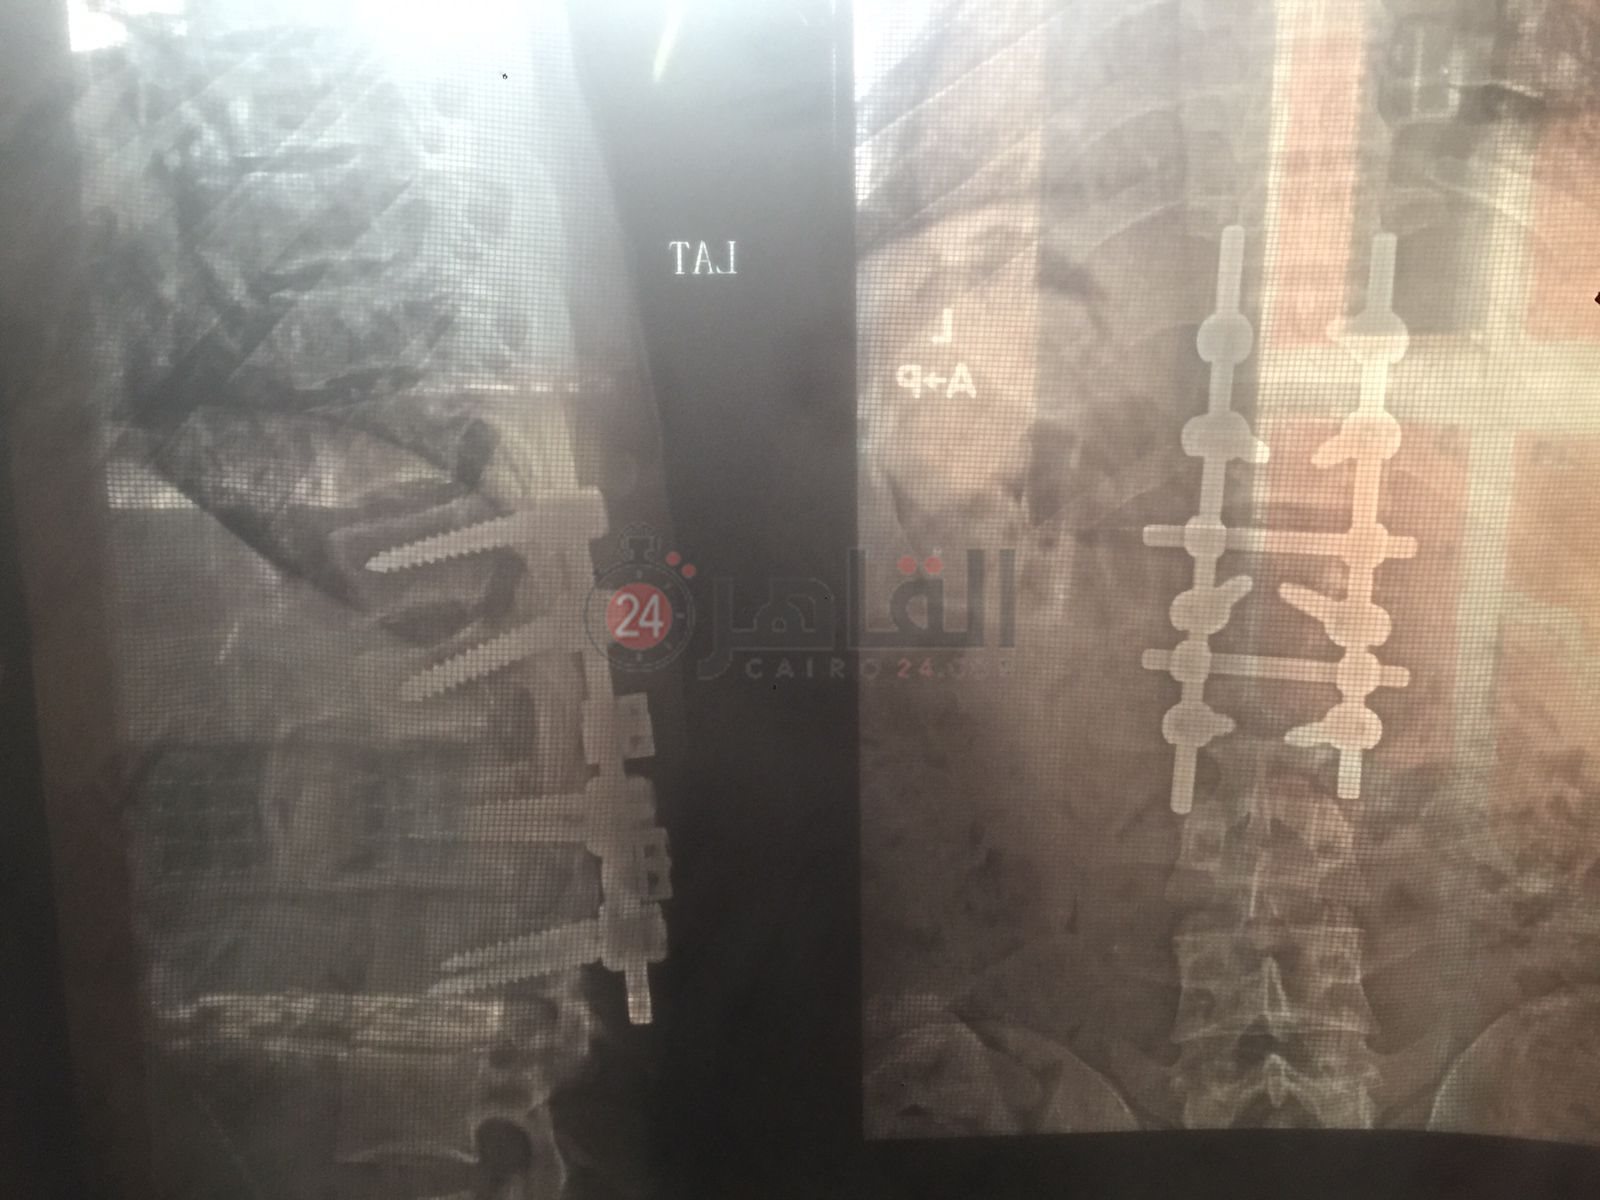

وتابع صلاح: كنتٌ أعمل بإحدى شركات الخدمات البترولية، وسقط عليّ 2 طن حديد، مما أدى إلى كسر الفقرة القطنية، مع الضغط الشديد على النخاع الشوكي، الأمر الذي أدى إلى إصابتي بضمور العضلات.